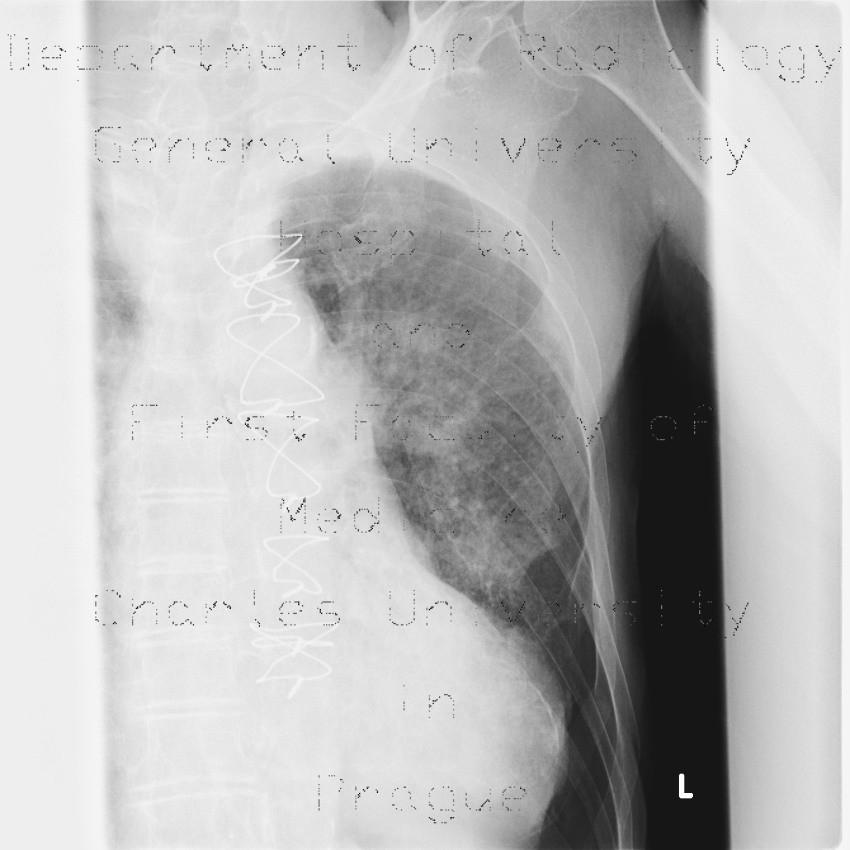

From atlas.mudr.org

Radiology case Rib fracture, lung contusion, hematoma, pneumothorax Rib Fracture And Pneumothorax How are rib fractures diagnosed? Learn about the causes, symptoms, diagnosis and treatment of rib fractures and pneumothorax, a collapsed lung. Rib fractures can also lead to a collapsed lung (sometimes called pneumothorax). Multiple rib fractures (≥3) or fractures in the upper or lower rib cage are associated with internal injuries such as liver or. The lung center at bwh. Rib Fracture And Pneumothorax.